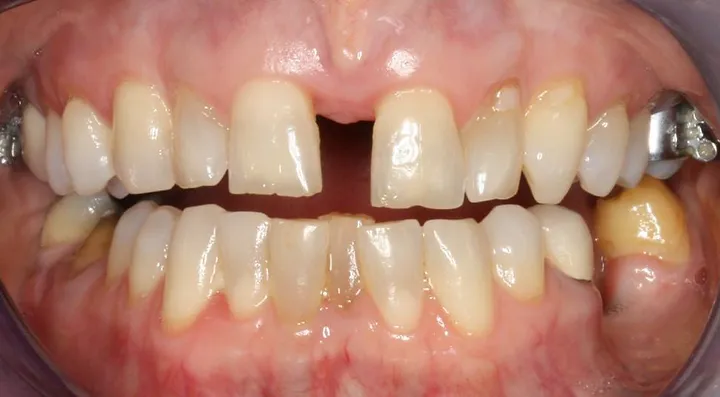

if you have bad transverse maxillary deficiency then definitely look into it. i want to try and get this however i dont know if i'll be eligible seeing as how my lower arch is like 10mm smaller than my maxillary arch.

look how the maxilla was ripped apart on this one holy chit